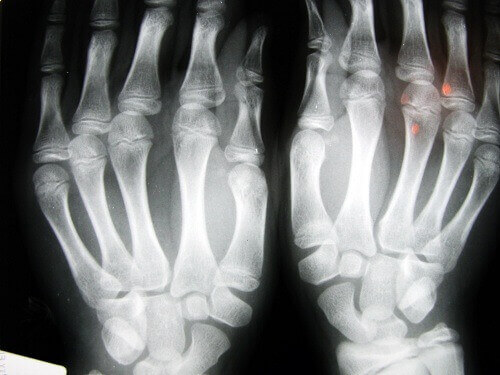

- Een van de best bekende studies over dit onderwerp is uitgevoerd door dr. Donald Unger. Hij kraakte meer dan 60 jaar achter elkaar twee keer per dag de vingers van zijn linkerhand. Dit deed hij echter niet met zijn rechterhand. Elk jaar onderzocht hij zijn handen. Hij vond nooit een aanwijzing van een degeneratieve ziekte, zelfs niet in de hand die hij kraakte.

- In een ander onderzoek werden dertig bejaarde personen in een bejaardenhuis in Los Angeles onderzocht. De personen die hun hele leven al hun knokkels kraakten hadden geen artrose.

- In een derde onderzoek, dit keer met volwassenen in Detroit die 45 jaar oud waren. Hier werd ontdekt dat het grootste probleem het verlies in kracht van hun grip was. Meer dan 80% van de onderzochte personen had last van opgezwollen handen.